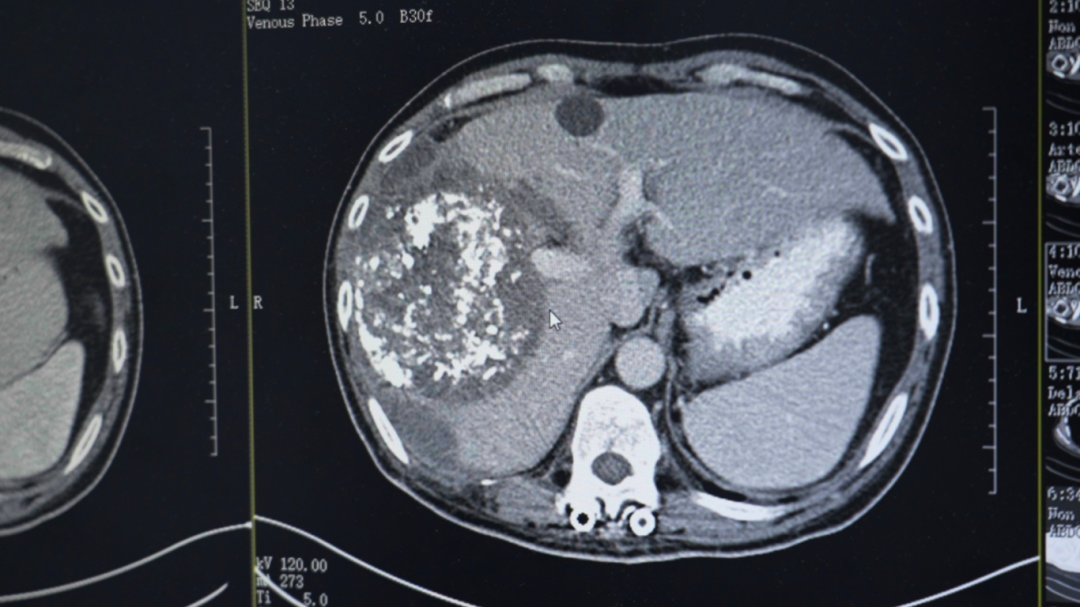

在当地医院,勇哥接受了一次介入灌注化疗栓塞术,但反应剧烈,“反复发烧,烧了足足半个月”。好不容易烧退了,复查结果却更令人绝望:肝脏病灶扩大到13.2厘米,肺转移瘤增多,肝门区、腹腔淋巴结密密麻麻。医生跟他说肿瘤扩散太广,无法手术,最多只剩“两个月时间”。

第三次回院复查时,勇哥的甲胎蛋白已降至800多,CT显示肝癌及肝内多发转移瘤、双肺转移瘤及大网膜转移瘤都较前缩小,无新发病灶,病情评价为稳定(SD)。“这次做介入治疗时,医生告诉我肝上肿瘤基本没有活性了。”勇哥的声音中带着久违的轻松。